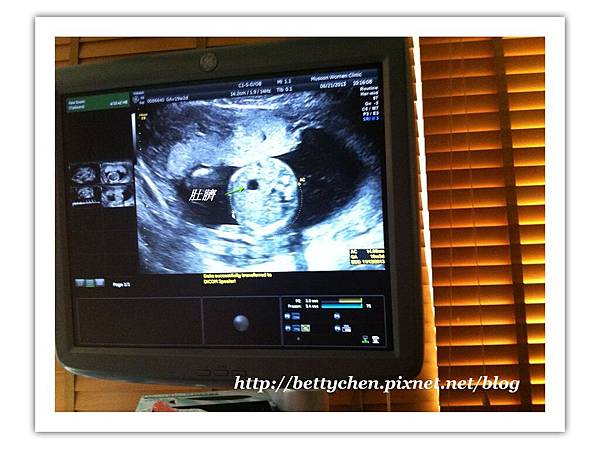

10

再來量肚圍,從中間的肚臍往外畫一個圓就是他的肚圍~~